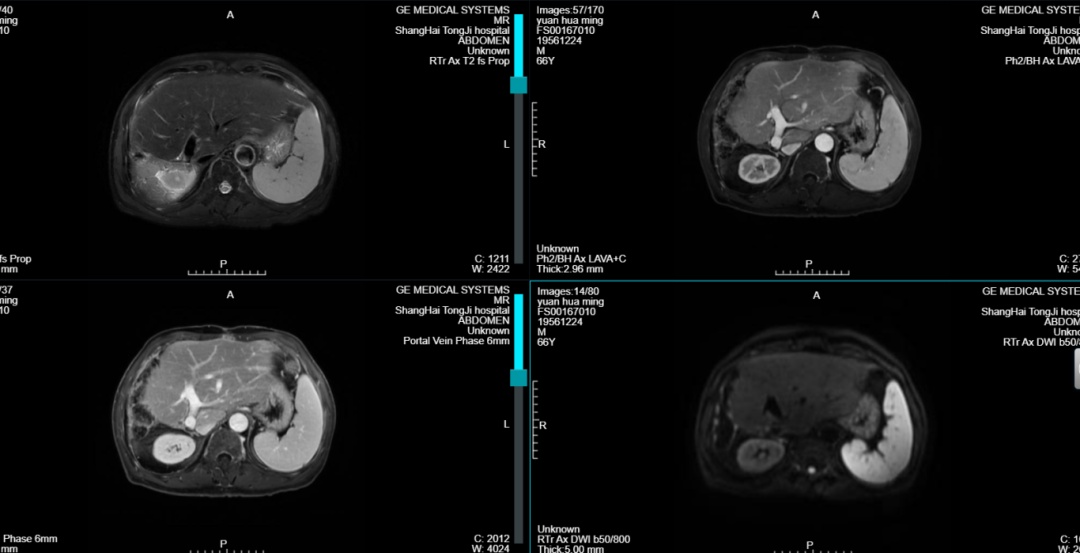

术后4个月和8个月复查,肿瘤指标甲胎蛋白(AFP)和异常凝血酶原均在正常范围内,复查MR检查提示左肝进一步增大,未见肿瘤复发。

术后4月复诊MR图

术后8月复诊MR图